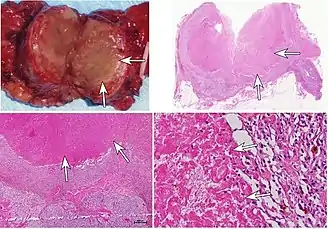

Macroscopic

The macroscopic appearance of an area of coagulative necrosis is a pale segment of tissue contrasting against surrounding well vascularized tissue and is dry on cut surface. The tissue may later turn red due to inflammatory response. The surrounding surviving cells can aid in regeneration of the affected tissue unless they are stable or permanent.

Microscopic

Microscopically, coagulative necrosis causes cells to appear to have the same outline, but no nuclei.[2] The nucleus is lost and there is cytoplasmic hypereosinophilia on H&E stain.(Protein denaturation results in exposure of hydrophobic regions normally sequestered within the three-dimensional center of the molecules and may explain why necrotic cells display an increased capacity to bind the hydrophobic Eosin pigment)[4] Also, it is characteristic of coagulative necrosis to not have a zone in between necrotic cells and viable cells. There is an instant transition, lacking granulation tissue in between.[5]